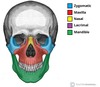

What are the main bones of the skull ?

What are the main bones of the skull (face)